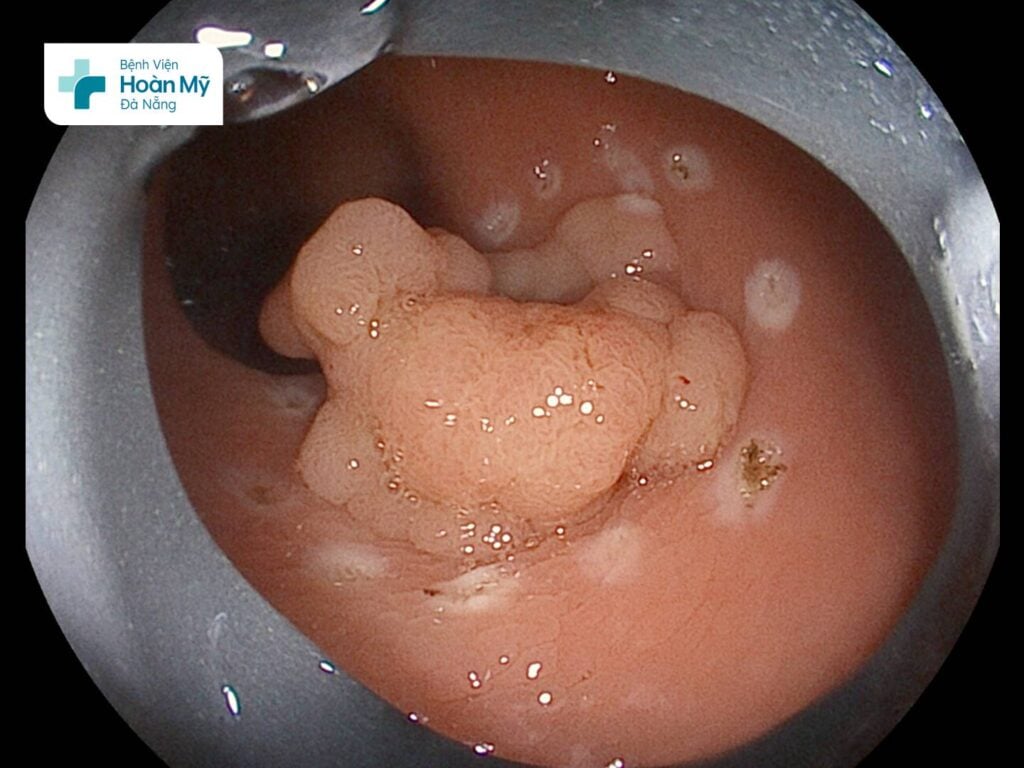

Qua nội soi phát hiện trực tràng có 1 thương tổn lan rộng (LST-G), kích thước khoảng 25 mm, bề mặt nhiều nốt không đều. Thương tổn này được bác sĩ nội soi lấy mẫu sinh thiết. Kết quả giải phẫu bệnh cho thấy đây là u tuyến ống kèm nghịch sản độ thấp. Thương tổn này nếu không được cắt bỏ sớm nguy cơ tiến thành ung thư rất cao.

Tổn thương tiền ung thư kích thước 25 mm, bề mặt nhiều nốt không đều tại trực tràng của người bệnh

Các bác sĩ đánh giá đây là tổn thương tiền ung thư của trực tràng. Trên cơ sở hội chẩn với các chuyên khoa, các bác sĩ đã thống nhất chỉ định nội soi can thiệp cắt tách dưới niêm mạc (ESD) để loại bỏ tổn thương tiền ung thư.